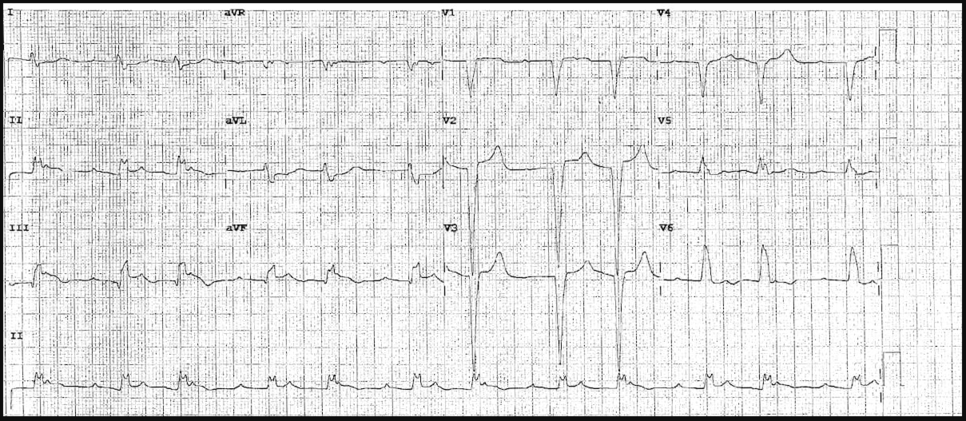

There is 1mm concordant ST elevation in aVL (= 5 points)

There is concordant ST depression in V2-5 (= Sgarbossa positive).